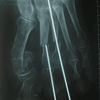

RESULTADOS

Caso 1: Hallux Valgus del Adulto